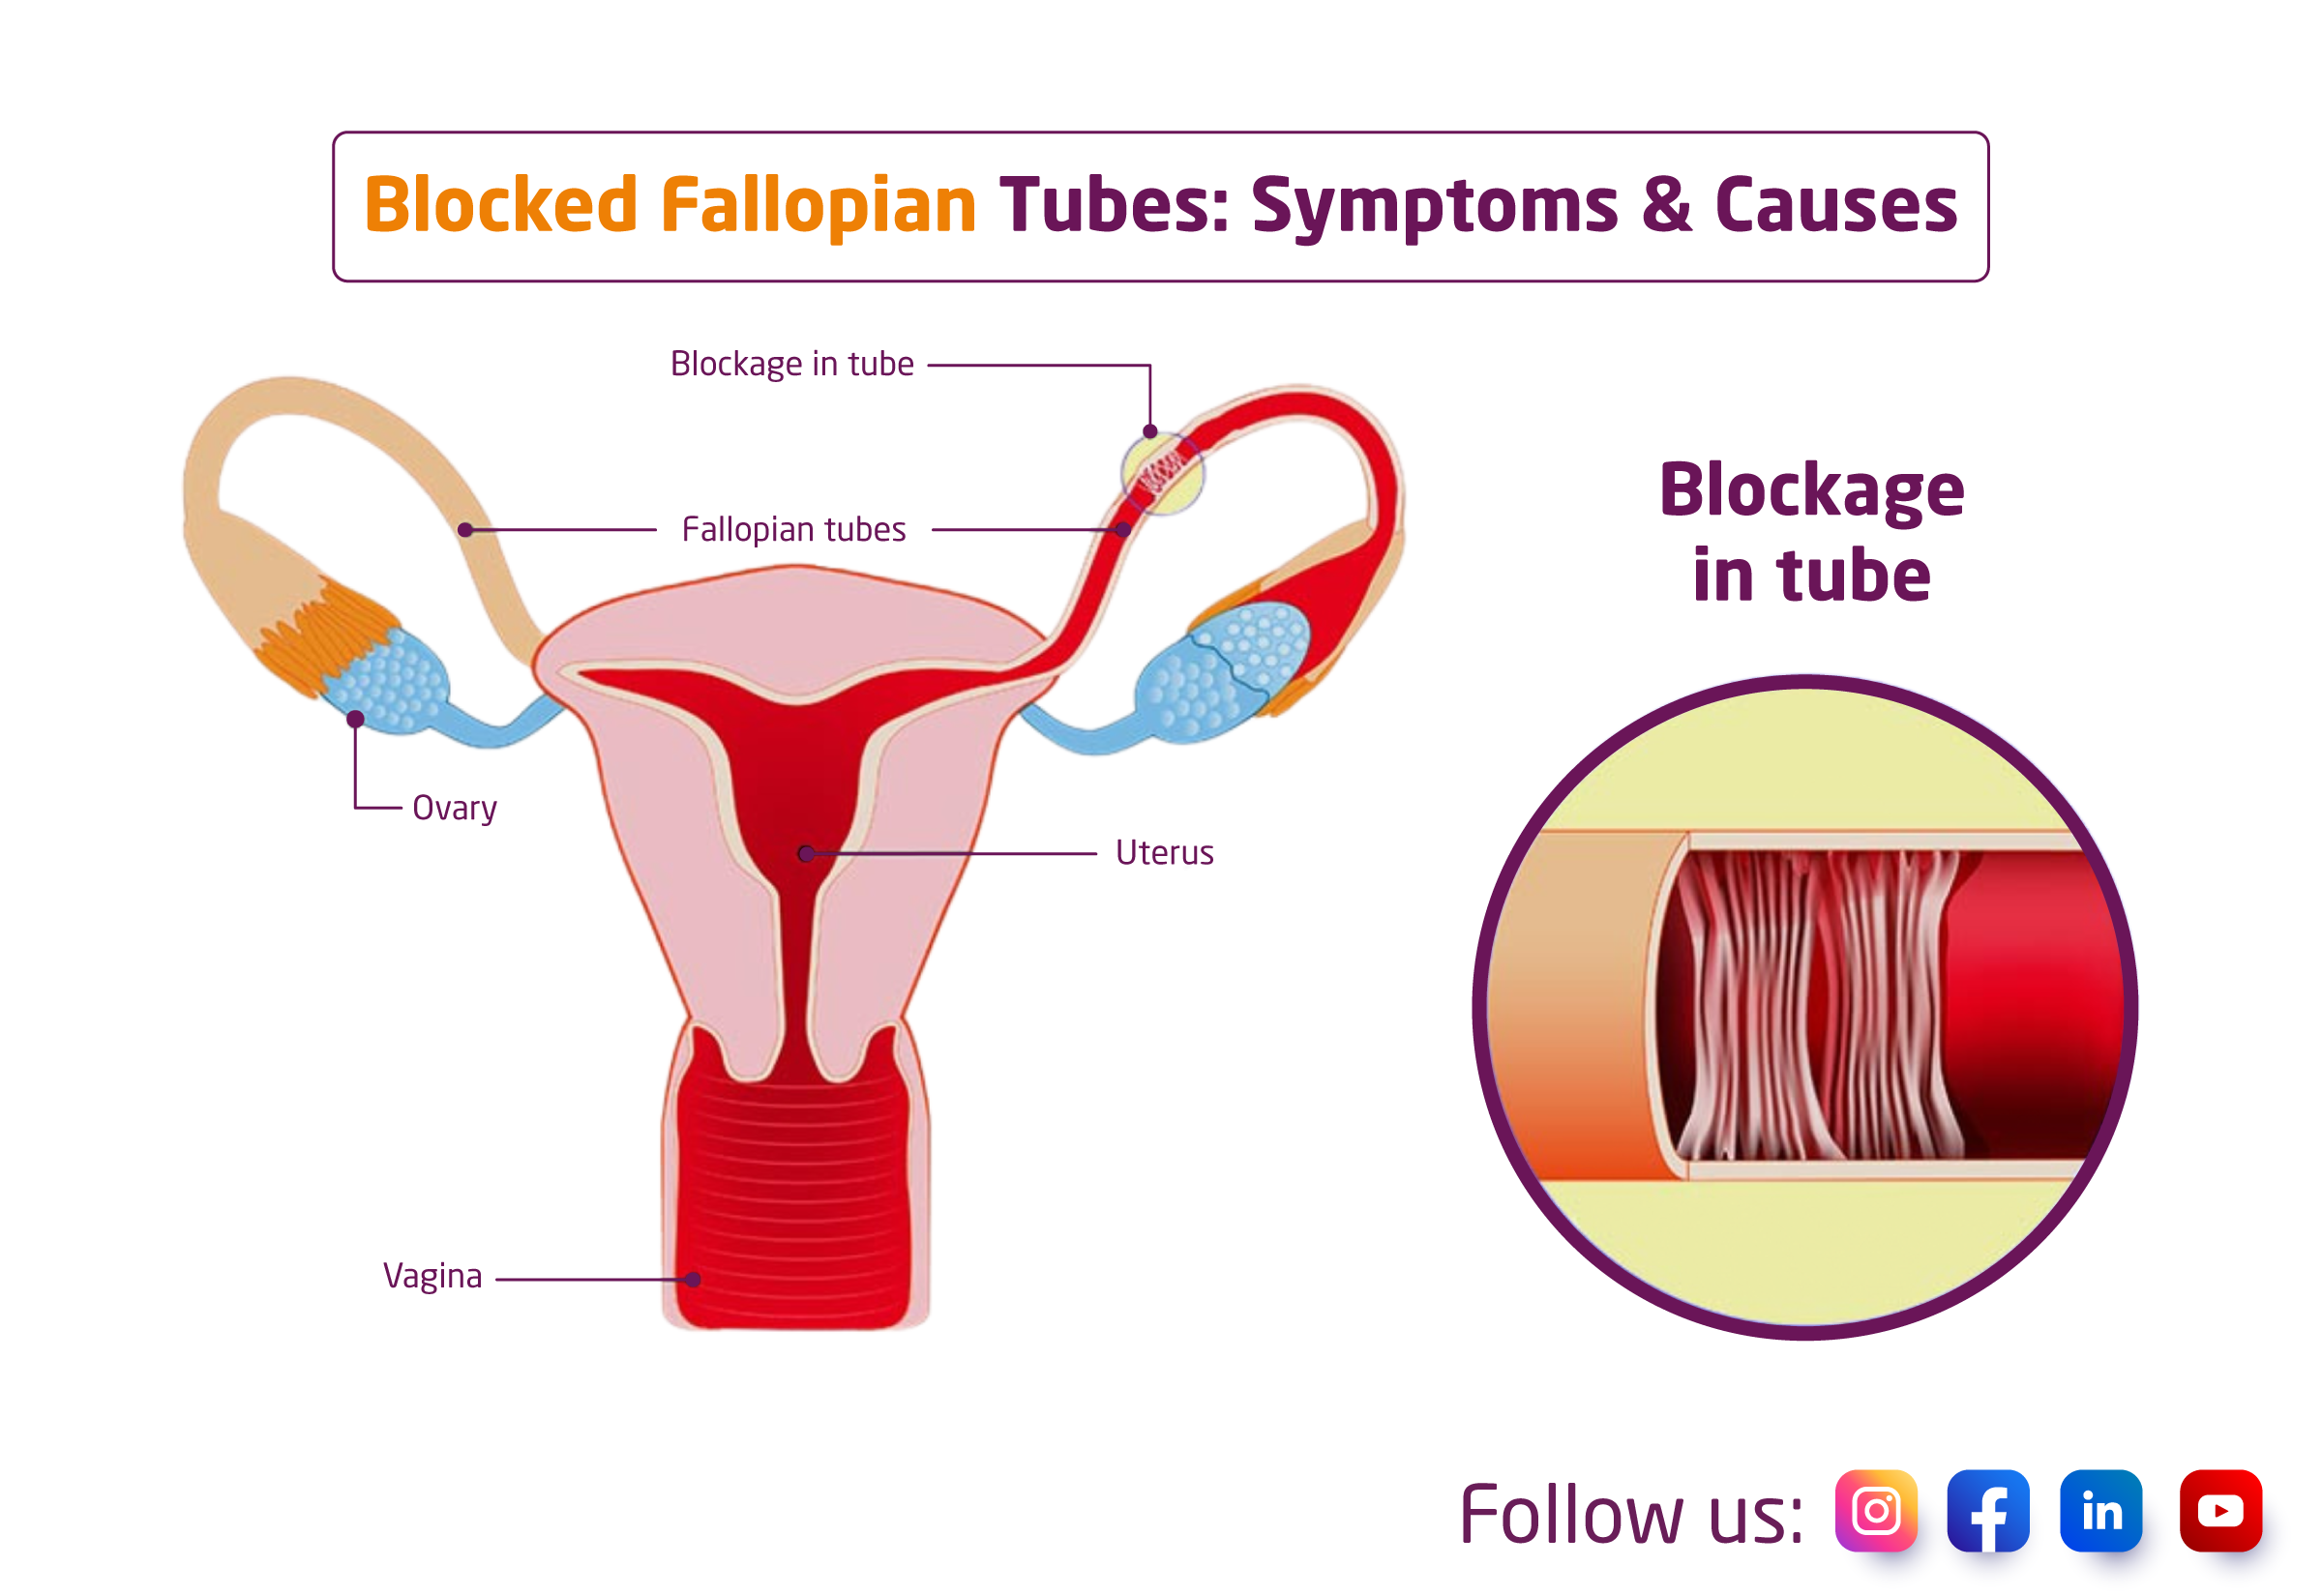

Blocked Fallopian Tubes Causes Symptoms And Treatment

Blocked Fallopian Tubes Symptoms Causes And Treatment

FTR Symptoms And Causes Of Blocked Fallopian Tubes Fibroid

Fallopian Tube Blockage Natural Treatment